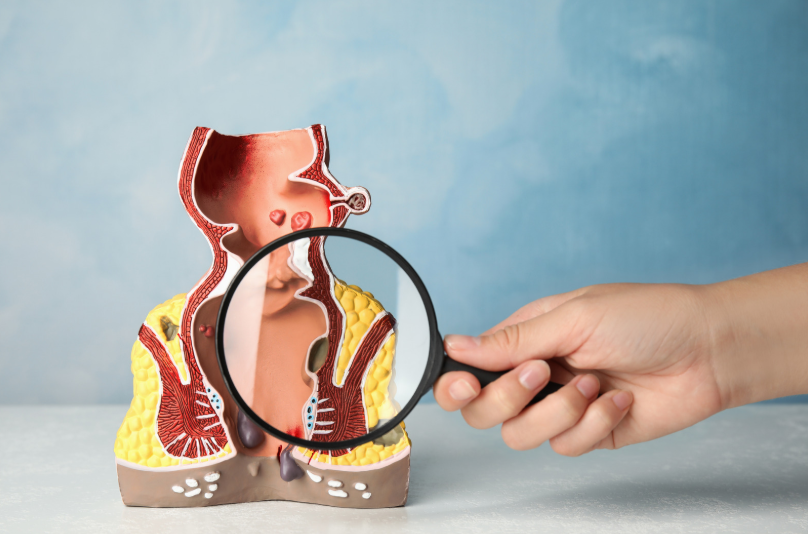

What Happens During Anal Fistula Repair and Removal in the Philippines

Anal Fistula Repair and Removal in the Philippines refers to a set of surgical procedures used to treat abnormal tunnels that form between the anal canal and the skin near the anus. These tunnels often develop after infection or abscess and can lead to ongoing discomfort, drainage, and repeated inflammation. Many patients delay consultation due […]